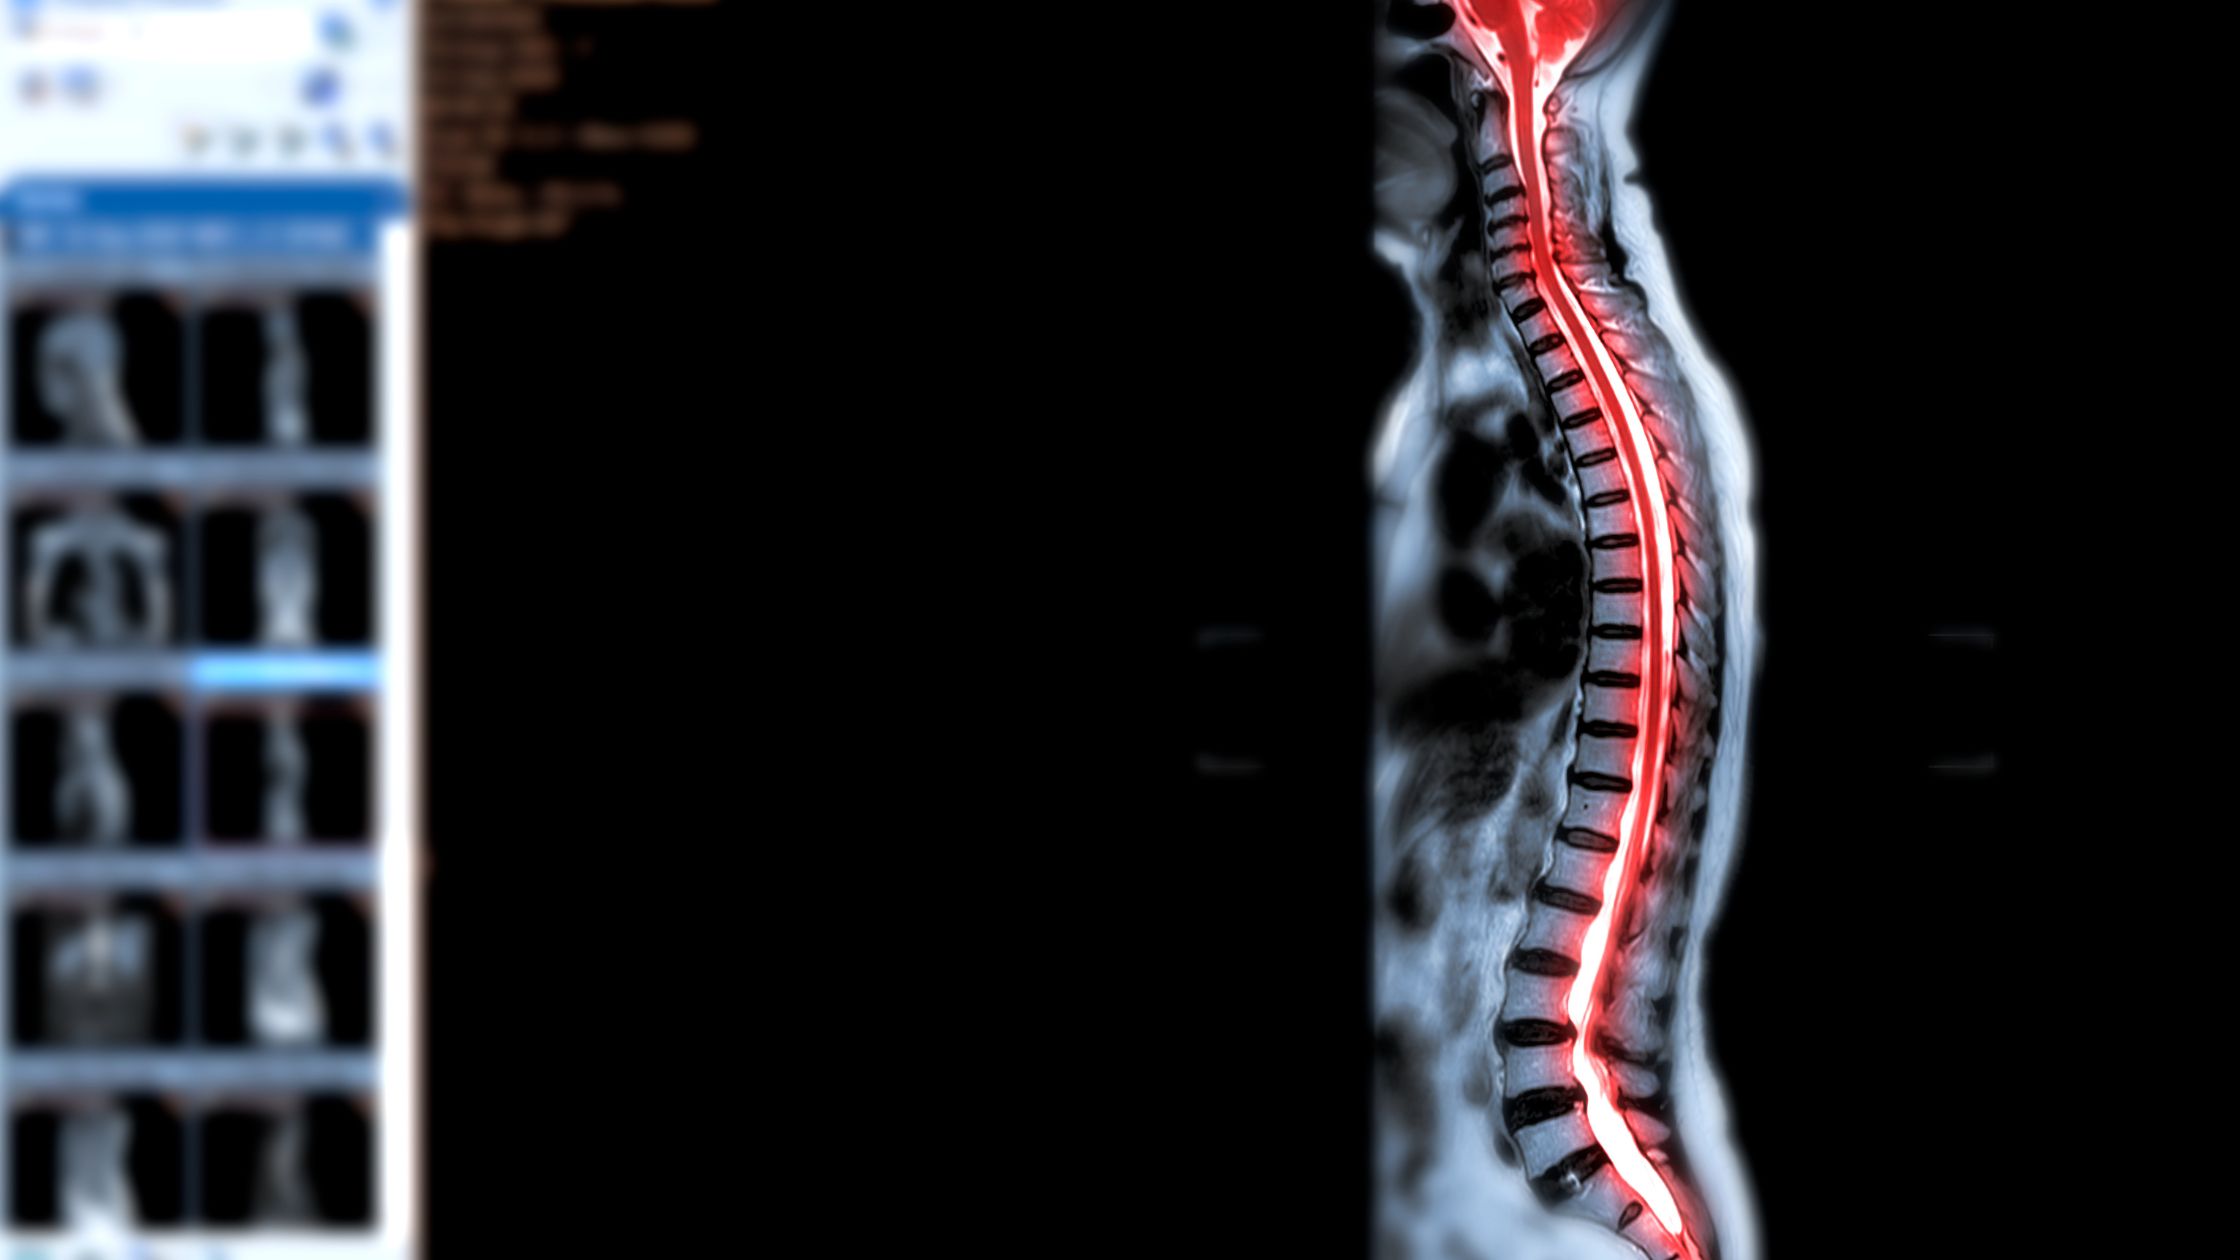

استشاري جراحة المخ والأعصاب و العمود الفقري

أستاذ و استشاري جراحات المخ و الاعصاب والعمود الفقري بالقصر العيني